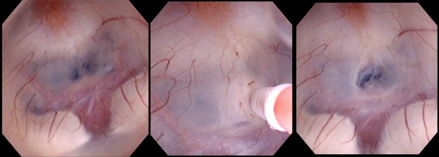

神経内視鏡を用いた第三脳室底開窓術

頭蓋骨に小さな穴をあけて脳室に内視鏡を挿入し、脳室と脳槽を隔てる薄い膜に孔をあけ新しい髄液の通路を作成し圧の不均衡を改善する手術です。

シャントなどの異物を体内へ入れる必要はない利点はるものの、年齢や水頭症の原因によって効果が制限されます。手術方法の選択に関しては十分な検討が必要です。